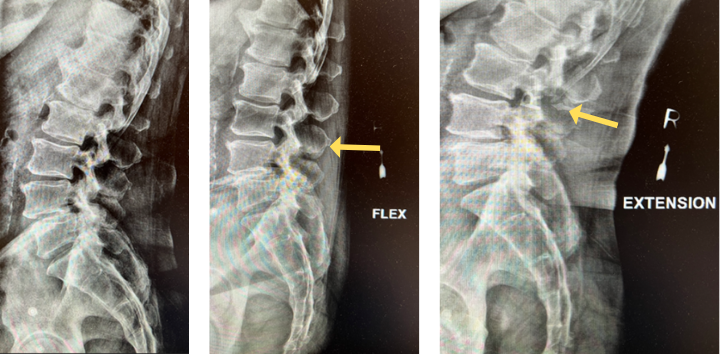

Image 3. Post-op x-rays that show L4/L5 transforaminal lumbar interbody fusion (TLIF). There was also removal the L2/L3 disc herniation but no need for instrumentation.

Dr. Imani was able to decompress both the L2/L3 level (with disc herniation removal) and the L4/L5 level. Additionally, L4/L5 level was fused using titanium screw and an expandable interbody cage. This was performed with a very small incision. The patient has no more leg pain and back pain, and is doing very well!